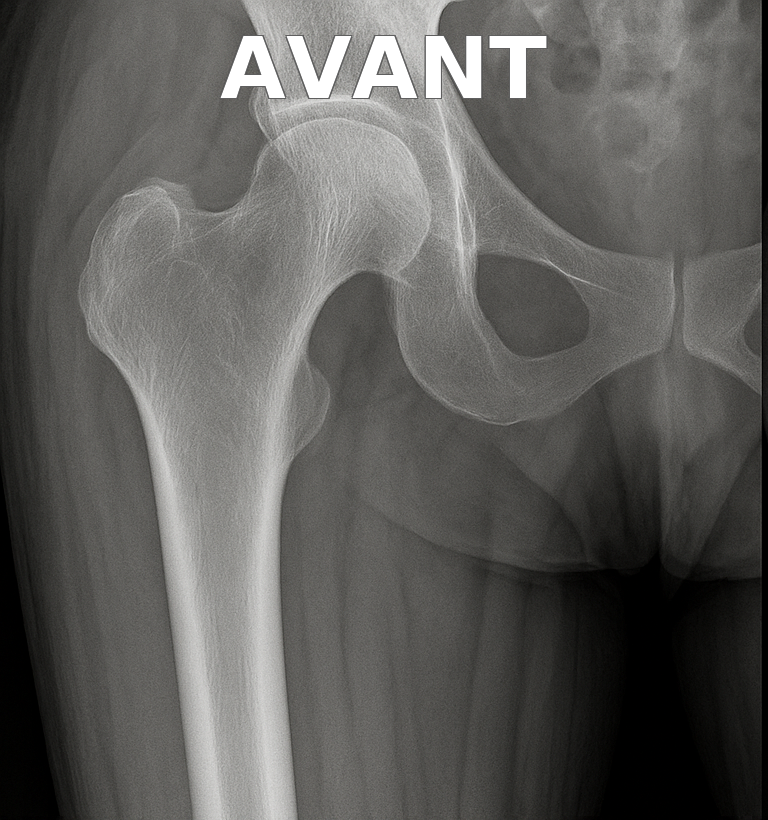

Illustration radiologique

Prothèse de hanche